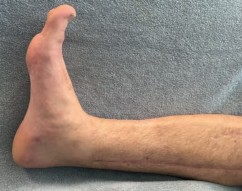

In cases involving acute compartment syndrome, the sequelae can be particularly devastating. Even with prompt fasciotomy, some degree of muscle necrosis may occur, leading to late fibrotic contractures, particularly of the deep posterior compartment (resulting in claw toes and equinus contracture). Neurologic deficits, such as foot drop from deep peroneal nerve ischemia, may be permanent, necessitating subsequent tendon transfers or ankle-foot orthoses (AFOs).

Image

When joint-preserving procedures fail due to advanced post-traumatic osteoarthritis, severe avascular necrosis of the distal tibial block, or intractable deep infection, salvage management is required. Ankle arthrodesis remains the gold standard for painful, arthritic pilon nonunions. In cases of massive bone loss or recalcitrant infection, a tibiotalocalcaneal (TTC) fusion utilizing a retrograde intramedullary nail or a circular external fixator with bone transport may be necessary to salvage a functional, plantigrade limb. In the most extreme cases, where limb salvage has failed after multiple reconstructive attempts, a below-knee amputation (BKA) may provide the patient with the highest functional outcome and quality of life.